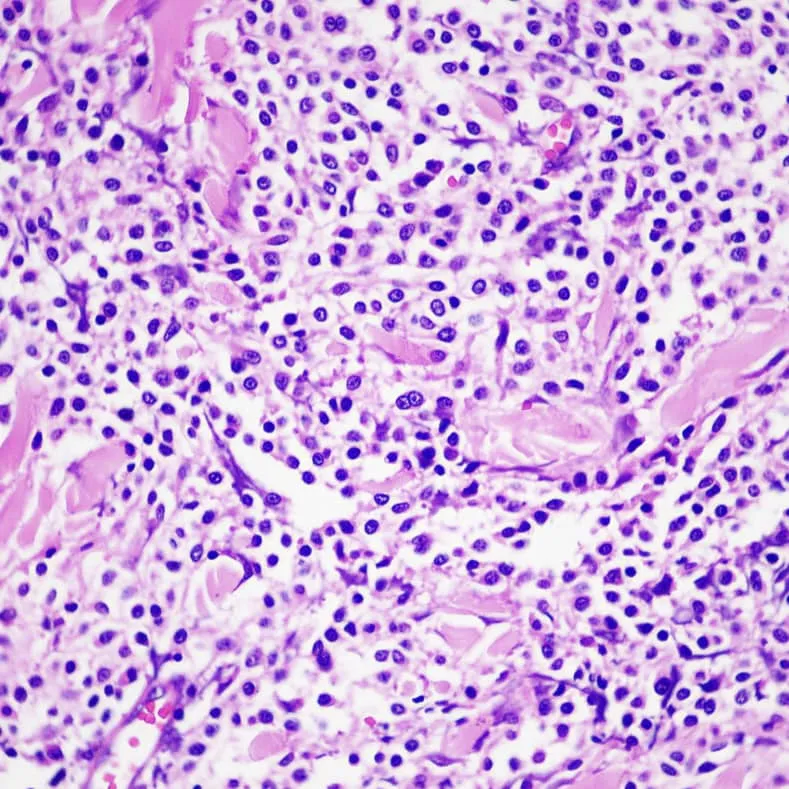

1. 經過採樣診斷:確認為肥大細胞瘤。